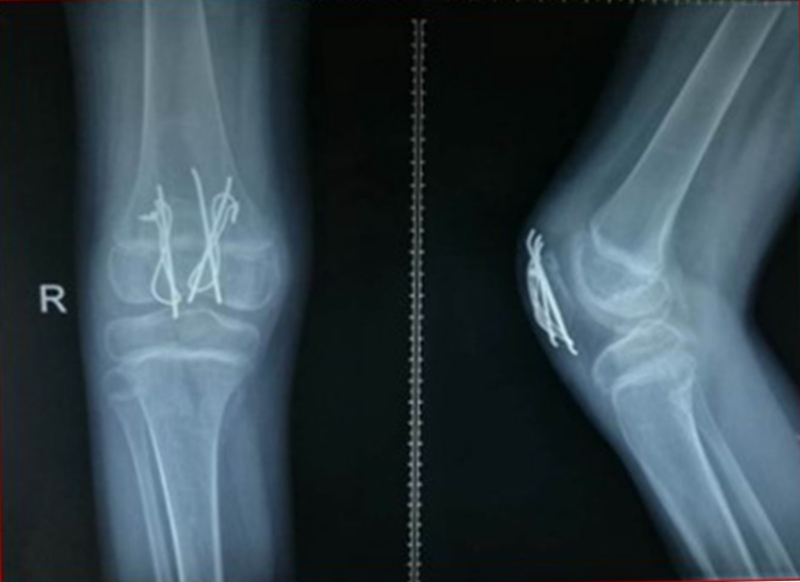

图7 术中X线

图8 术后石膏固定X线